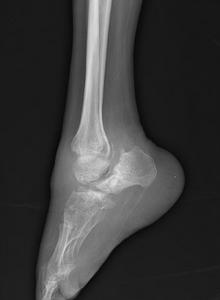

X線所見為伴有滑膜滲出的關節膨大和關節面不全脫位。通常能見到骨端硬化,但在晚期破壞性病變中也可能看不到。骨骼畸形,並在鄰近皮質的地方有明顯的新骨形成。這種新骨形成開始發生在關節囊內,然後常常向上擴展到長骨骨幹。軟組織偶可出現骨化和鈣化現象,然而這種現象可能是暫時的,甚至軟組織廣泛鈣化在隨後拍攝的X線照片上也可能消失。關節邊緣可見到形狀不規則的巨大骨贅,脫落後形成大量關節內游離體,此為本病特徵性改變。脊柱受累的X線表現(即特徵性的“鸚鵡嘴”樣骨贅),就是在缺乏局部臨床症候的情況下也十分常見。

X線檢查,早期見軟組織腫脹,骨端緻密,晚期關節顯示不同程度的破壞,間隙狹窄,骨端緻密,病理骨折,關節內游離體,骨質吸收,退變骨贅和新骨形成,以及關節脫位與畸形。